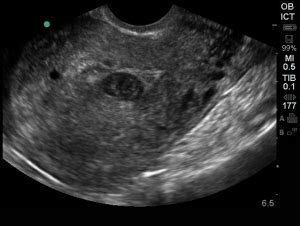

So, let’s break down the nitty-gritty: how do doctors tell the difference between a pseudogestational sac and the real deal , the true gestational sac that’s nurturing your future little one? Guys, this is where the magic of ultrasound and the expertise of medical professionals really shine. It’s not just about seeing a sac; it’s about what kind of sac it is and what’s inside it. A true gestational sac is the very first structure that becomes visible on an ultrasound in early pregnancy, usually around 5 weeks gestation. It’s a round or oval-shaped cavity within the decidua (the specialized lining of the uterus during pregnancy). Crucially, a true gestational sac will contain a yolk sac , and shortly after, an embryo . The yolk sac is vital because it provides nourishment to the developing embryo in these earliest stages. The sac itself typically has a distinct, thick, echogenic (bright) rim, which represents the early developing chorionic villi and decidua. Think of it as having a defined, well-formed boundary. On the other hand, a pseudogestational sac is an intra-uterine fluid collection . It forms because the decidua reacts to pregnancy hormones by secreting fluid, which then pools in the center of the uterine cavity. Because it’s just fluid, it typically lacks that well-defined, thick, echogenic rim seen in a true sac. Instead, its walls are often thinner and less distinct. Furthermore, and this is the most important distinction, a pseudogestational sac will not contain a yolk sac or an embryo . It’s an empty space. Sometimes, you might see a double-lining appearance within the pseudogestational sac, which can be misleading, but it’s still not the characteristic thick, bright ring of a true gestational sac. The location can also be a clue. A true gestational sac is typically found implanted eccentrically within the uterine cavity – meaning it’s off to one side, nestled into the uterine lining. A pseudogestational sac, being a collection of fluid in the center, is often located more centrally within the uterus. Doctors use all these subtle clues together. They measure the size of the sac, assess the thickness and appearance of its walls, look for the presence and characteristics of a yolk sac and embryo, and note its position within the uterus. They also correlate these ultrasound findings with the patient’s hCG levels and menstrual history. For instance, if a woman’s hCG levels are high enough that a gestational sac should be visible (typically above 1500-2000 mIU/mL on a transvaginal ultrasound), but the ultrasound shows only a pseudogestational sac and no intrauterine pregnancy, it raises a significant concern for either an early, non-viable intrauterine pregnancy or an ectopic pregnancy . This careful differentiation is absolutely paramount for guiding the correct medical management and ensuring the best possible outcome for the patient.

So, how do doctors figure out if what they’re seeing on the ultrasound is a pseudogestational sac or a real pregnancy sac? Guys, the diagnostic process is usually quite straightforward, but it relies heavily on a combination of imaging and biological markers. The primary tool is, of course, the ultrasound. When a woman presents with symptoms of early pregnancy, such as a missed period, spotting, or pelvic pain, and her pregnancy test (the hCG blood test) is positive, an ultrasound is typically ordered to confirm the location and viability of the pregnancy. During the ultrasound, the sonographer or radiologist will carefully examine the uterus. They are looking for the presence of a gestational sac. If a sac-like structure is seen, they will meticulously assess its characteristics. As we discussed, a true gestational sac is typically round or oval, implanted eccentrically within the uterine lining, and has a thick, bright (echogenic) wall. Most importantly, it will contain a visible yolk sac and, by a certain stage (usually around 6-7 weeks), an embryo with cardiac activity. In contrast, a pseudogestational sac will often appear more irregular in shape, located more centrally in the uterus, and will have thinner, less defined walls. The defining feature is the absence of a yolk sac or embryo within it. The surrounding fluid might also appear different. hCG levels play a crucial supporting role in this diagnosis. Human chorionic gonadotropin (hCG) is the hormone detected by pregnancy tests. In a normal intrauterine pregnancy, hCG levels typically double every 48-72 hours in the early weeks. Doctors use these levels in conjunction with ultrasound findings. There’s a